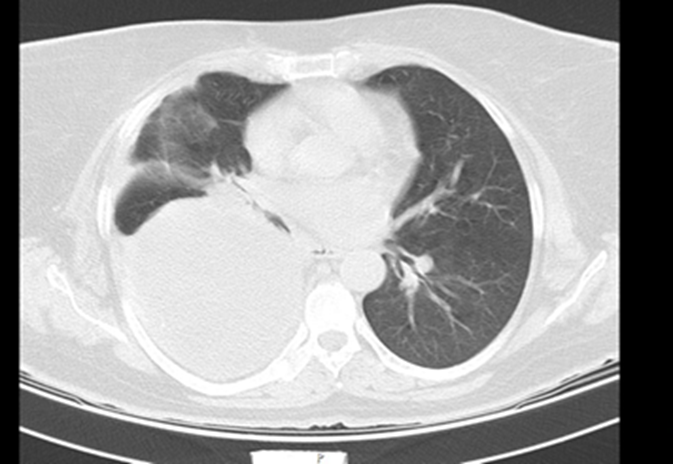

A 58-year-old woman was refered to our hospital with a history of recurrent right side chest wall pain ,cough ,night sweating ,hemoptysis and dyspnea for 4-6 weeks. A physical examination revealed respiratory sounds were decreased on the middle right side of chest. His complete blood count, erythrocyte sedimentation rate, CRP blood urea nitrogen (BUN) level, and creatinine level were normal and liver function tests (AST,ALT ,AKP and bilirubin ) and anti hydatid tests were normal . Poster anterior (PA) and lateral chest radiographs were performed . The PA chest radiograph (Figure 1)showed a well-defined 10- to 14-cm right paracardiac cystic mass located in the right middle zone of chest. The CT-scan showed a large well –defined hypo dense cystic mass measuring 112 mm is seen in superior segment of RUL.Sub segmental atelectasis also seen in right lung caused compressing. Left lung was normal . Figure 2(a,b,c,d,e,f,g,h,i) . In the CT –scan there was no invasion of the chest wall and others intrathoracic structures. CT images show no enlargement of lymph nodes and pleural effusion but lung parachymal was involved.The testes for hydatid cyst were negative .Ultrasonography of abdomen was normal . A classic right posterolateral thoracotomy in six intercostal space was performed. Around of cystic lesion was walling off with wet sponge with normal Saline (Fig 3). In the aspiration of the lesion there was a hemorrhagic dense viscous fluid .The cystic mass was completely removed without complications and free margin. On the operation time , macroscopic examination show hemorrhagic dense viscous fluid and debris was observed in the center of the lesion(Fig 4) Microscopic examination showed an encapsulated mesenchymal neoplasm composed of short fasciles of bland looking spindle cell which are diffusely positive for S100 and GEAP on immunohistochemically diagnosis was a schwannoma tumor. The patient was discharged on the 6 th postoperative day. The patient did not recurrence after 8 month of follow-up

Figure: 2 CT -scan A, B, C, D, E, F, G show solid cystic lesion.